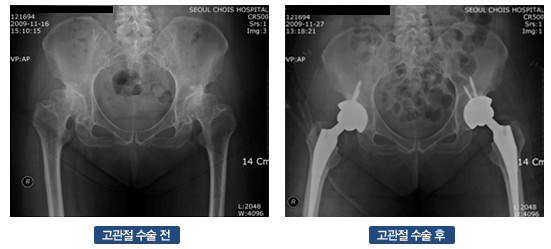

고관절 수술은 다양한 이유로 시행될 수 있지만, 일반적으로는 고관절 관절염, 외상, 또는 선천적인 기형 등으로 인해 통증이나 기능 저하가 나타날 때 이루어집니다. 이 수술에는 인공관절 치환술, 관절경 수술 등의 방법이 있으며, 각각의 수술 방법은 회복 단계와 필요한 시간에 서로 영향을 미칩니다. 고관절 수술의 주된 목적은 통증을 감소시키고, 이동성과 일상생활의 질을 향상시키는 것입니다. 그러므로, 환자는 수술 후 생활 습관을 조절하고, 적극적인 rehabilitative 간호를 통해 빠른 회복을 도모해야 합니다.

- 인공관절 치환술: 가장 일반적인 고관절 수술입니다. 퇴행성 관절염이나 심한 외상으로 인해 고관절이 손상된 경우, 인공 관절로 대체합니다. 이 수술은 대개 1-2시간 가량 소요되며, 회복이 길어질 수 있습니다.

- 진단적 검사: 의사가 필요할 경우 정기적으로 X-ray나 MRI를 통해 관절의 상태를 체크할 수 있습니다.